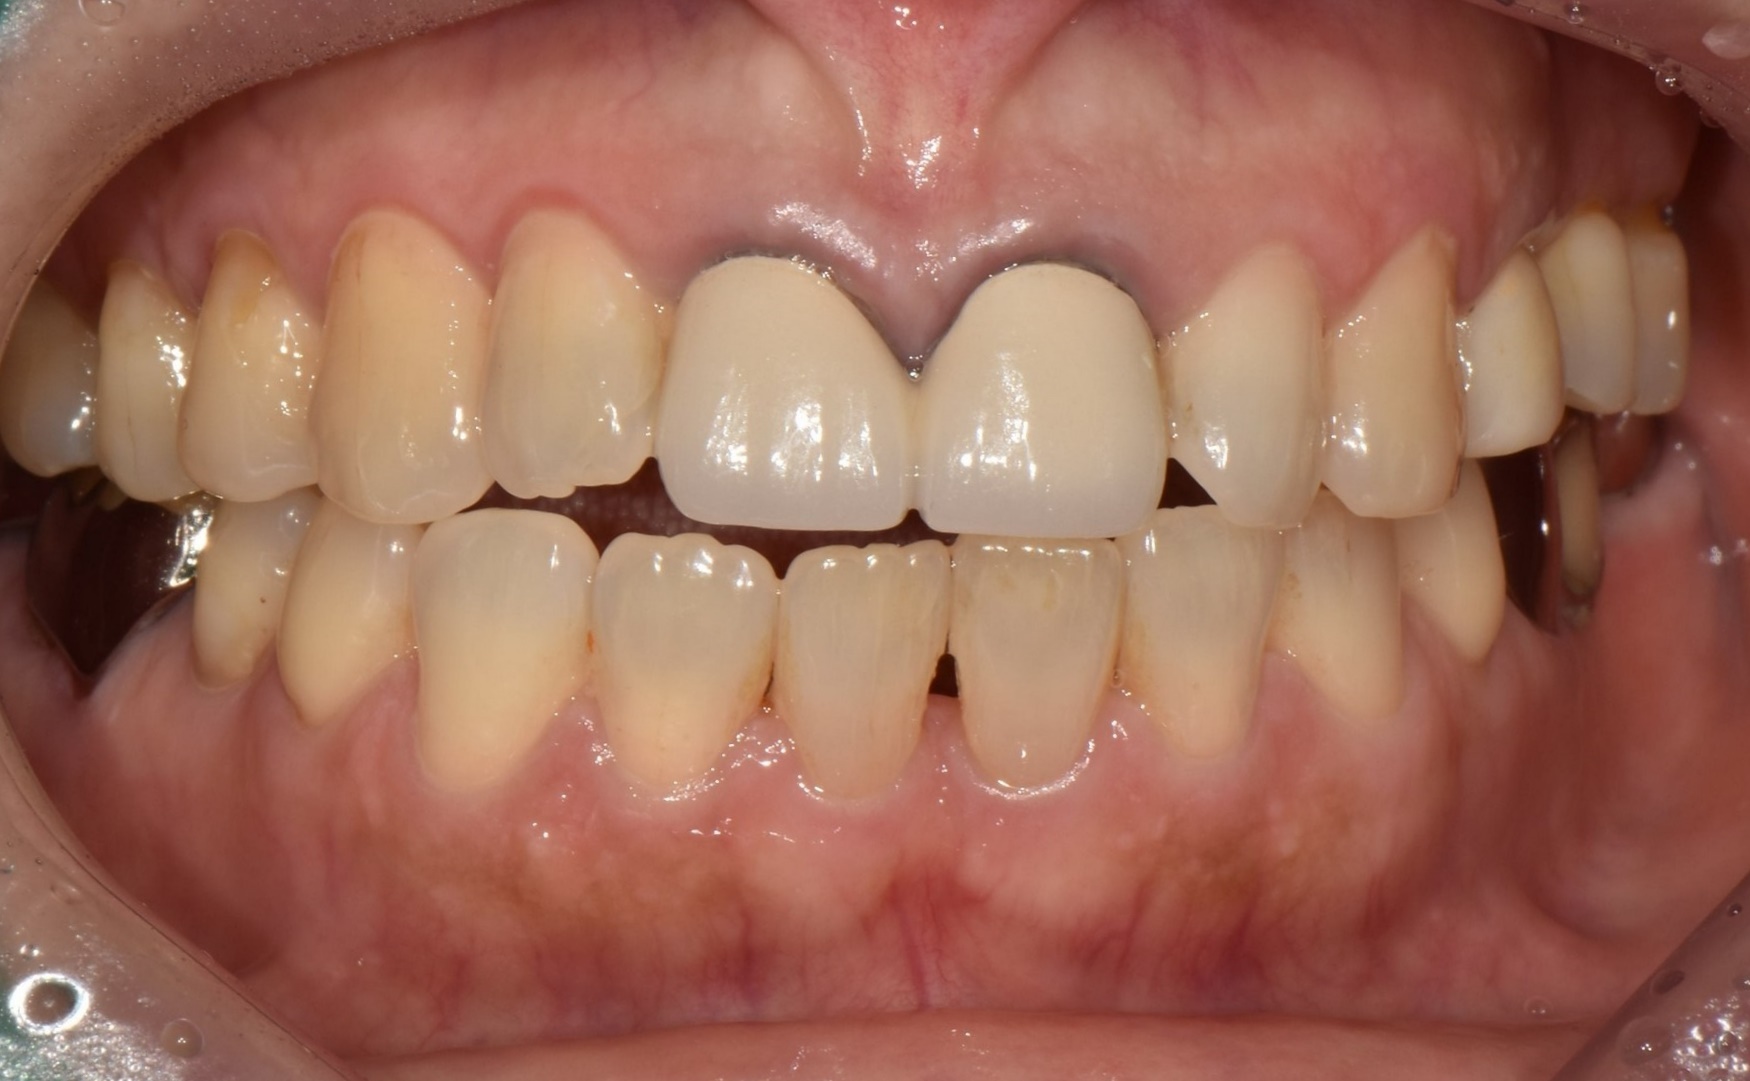

수술 전

수술 후

전치부 크라운 수복 사례

전후사진